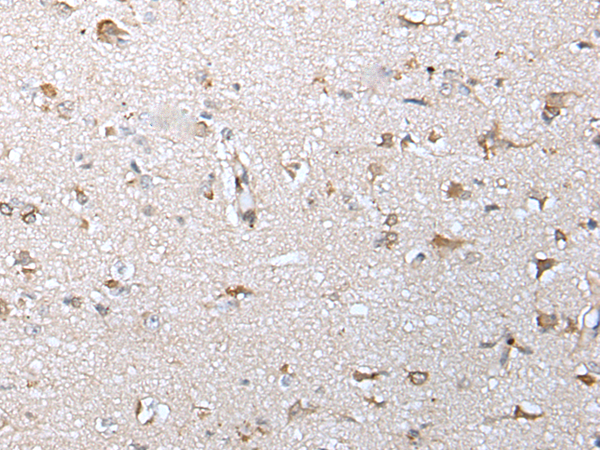

分类: 科研抗体货号: P12749别名: EL52; HSPN; LAP2; HSP86; HSPC1; HSPCA; Hsp89; Hsp90; LAP-2; HSP89A; HSP90A; HSP90N; Hsp103; HSPCAL1; HSPCAL4; HEL-S-65p应用: IHC反应种属: Human, Mouse, Rat